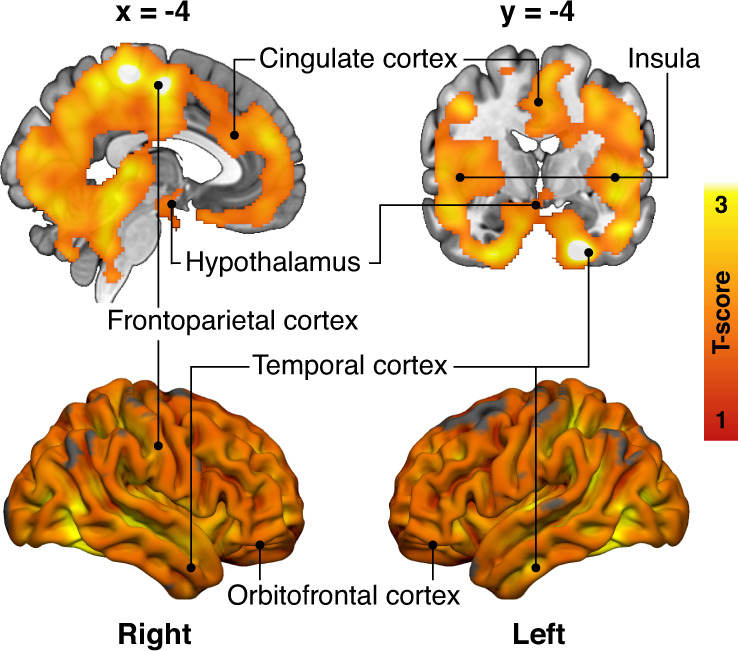

HR group had increased BGU compared to the LR group in multiple brain regions. Prominent associations were found in frontotemporal and cingulate cortices, hypothalamus, and bilaterally in insula and putamen (Fig. 2). MOR or CB1R availabilities did not have statistically significant differences between the two groups.